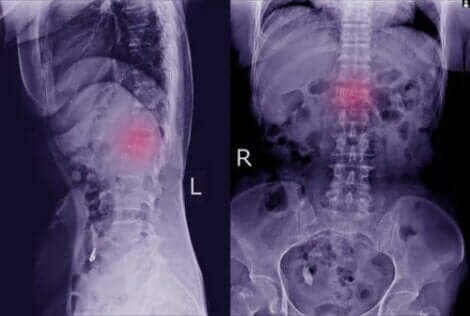

Diese körperlichen Manifestationen sind leicht zu übersehen. Wenn du jedoch darauf achtest, kannst du damit zu deinem Arzt gehen, um eine Röntgenaufnahme durchführen zu lassen. Dies ist der wichtigste Test bei der Erkennung dieses Leidens und der Arzt kann klar erkennen, ob ein Wirbel verschoben ist.

In einigen Fällen kann der Arzt spezifischere Tests anfordern, wie zum Beispiel eine Computertopographie oder einen MRT-Scan. Mit diesen zusätzlichen Tests kann er deutlicher sehen, ob eine Spondylolisthese vorliegt und ob Knochen und Nerven betroffen sind.